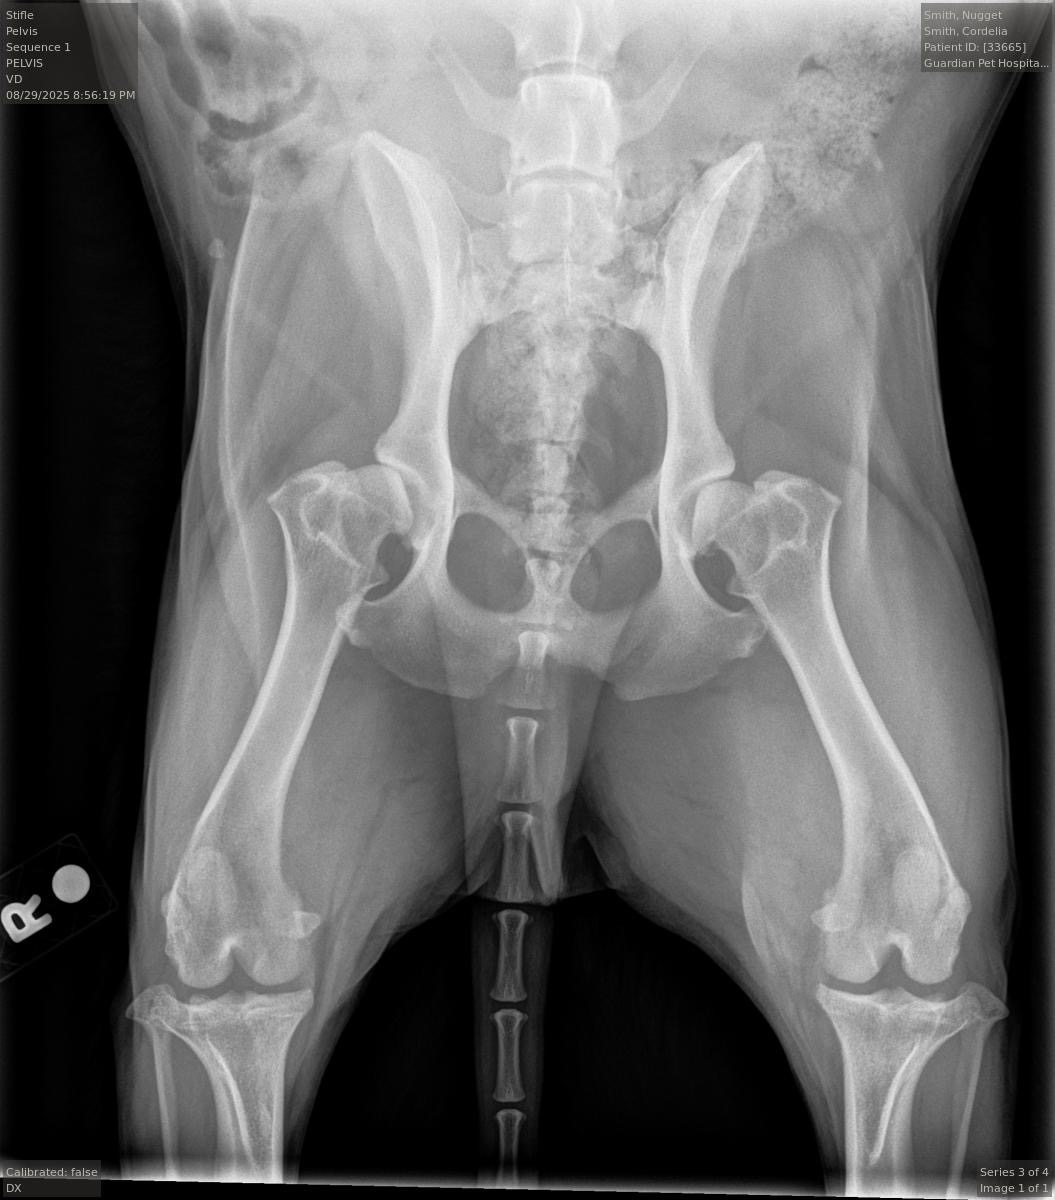

Unfortunately, we received Nugget’s X‑ray results and he will require TPLO surgery to fully recover from this injury-- it's like the same as tearing your ACL... Nugget has not been able to go for walks, jump onto the bed, or go to the dog park for about two months now. we were really hoping that it would heal on its own, but x-rays have identified that surgery is needed. . When we first started getting quotes around the DFW metroplex, most clinics estimated 5,000–7,000 for the surgery alone, not including postoperative care, medications, or follow‑up X‑rays.

After posting Nugget’s story less than 24 hours ago, many of you reached out with similar experiences and recommendations for clinics you’ve used for your own pets. With that information, we found a clinic in Austin that will perform the surgery and provide all postoperative care, medications, X‑rays, and physical therapy for half the price. Surgery is the first step. We’ve scheduled the operation for the end of this month, and recovery will take about 3–6 months.